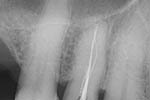

Revisionsbehandlung eines Unterkiefermolaren (37) vor geplanter Überkronung (Dr. Maik Göbbels) Download